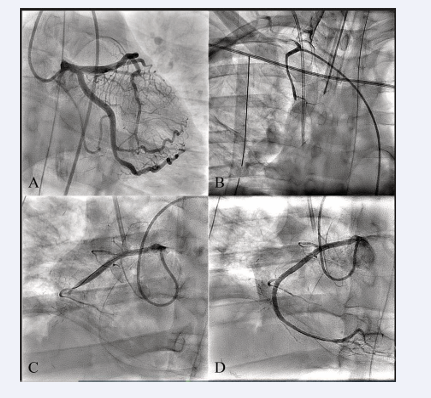

TTE showed akinesia of the basal to mid inferior wall with preserved left ventricular function. Urgent coronary angiogram showed patent left coronary system, total occlusion of the RIMA, and total thrombotic occlusion (TIMI 0 flow) of the mid RCA at the level of the anastomosis with the RIMA (Figure 3, Panel A, B & C; Videos 1 & 2).

After careful and quick discussion held between the cardiac surgeon and the interventional cardiologist, percutaneous coronary intervention (PCI) was carried on. Stenting to the RCA using two drug eluting stents was successfully performed and TIMI 3 flow was restored (Figure 3, Panel D; Video 3).

Coronary angiogram showing patent left coronary system (Panel A), total occlusion of the RIMA (Panel B; Video 1), and total thrombotic  occlusion (TIMI 0 flow) of the mid RCA at the level of the anastomosis with the RIMA (Panel C; Video 2). RCA post stenting with a TIMI 3 flow (Panel  D; Video 3).

Figure 3: Coronary angiogram showing patent left coronary system (Panel A), total occlusion of the RIMA (Panel B; Video 1), and total thrombotic occlusion (TIMI 0 flow) of the mid RCA at the level of the anastomosis with the RIMA (Panel C; Video 2). RCA post stenting with a TIMI 3 flow (Panel D; Video 3).